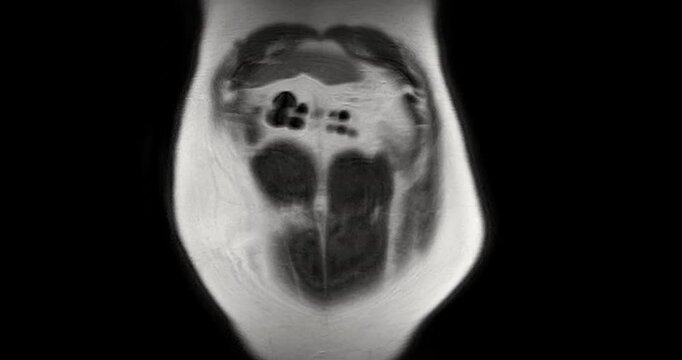

MRI whole abdomen video showing a fatty mass on the left side of the abdomen. Findings suggest a probable atypical lipomatous tumor, with differential diagnosis of well-differentiated liposarcoma.